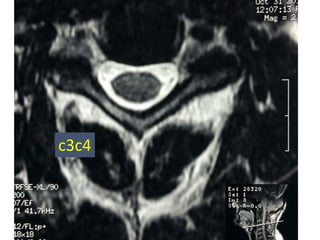

c3c4

77 year old woman with h/o hand weakness/numbness/ataxia

Prior acdf 14 years ago